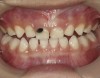

There is no consensus on the frequency of application, and 38% SDF has been used annually or biannually on clinical trials in children23,31,33,34 and in elderly.30,35 Yee and his co-worker found one-off application of 12% SDF was ineffective in arresting caries in children.31 The present authors applied 38% SDF weekly for 3 weeks to speed up the process of caries arrest and for treatment of rampant caries.36 One of the present authors’ case reports demonstrated that three weekly applications of 38% SDF can arrest rampant caries and relieve pain from hypersensitivity on a teenager. The SDF-treated caries were found arrested, and they turned coal black in appearance (Figure 9).